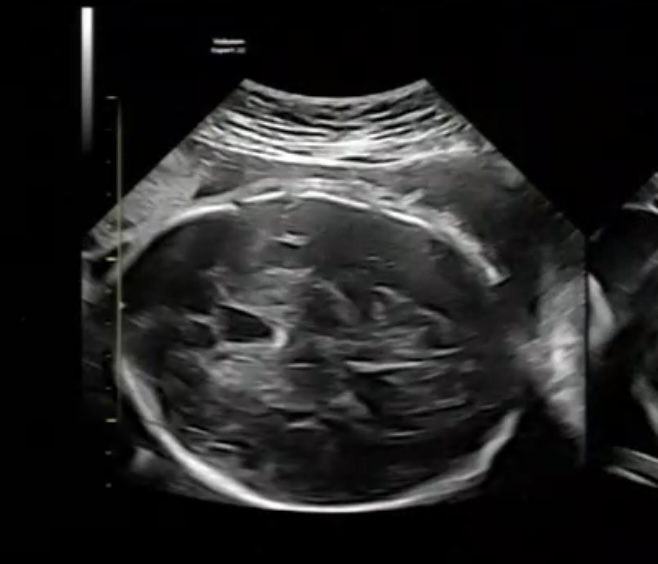

念の為、脳のエコー写真を添付します。